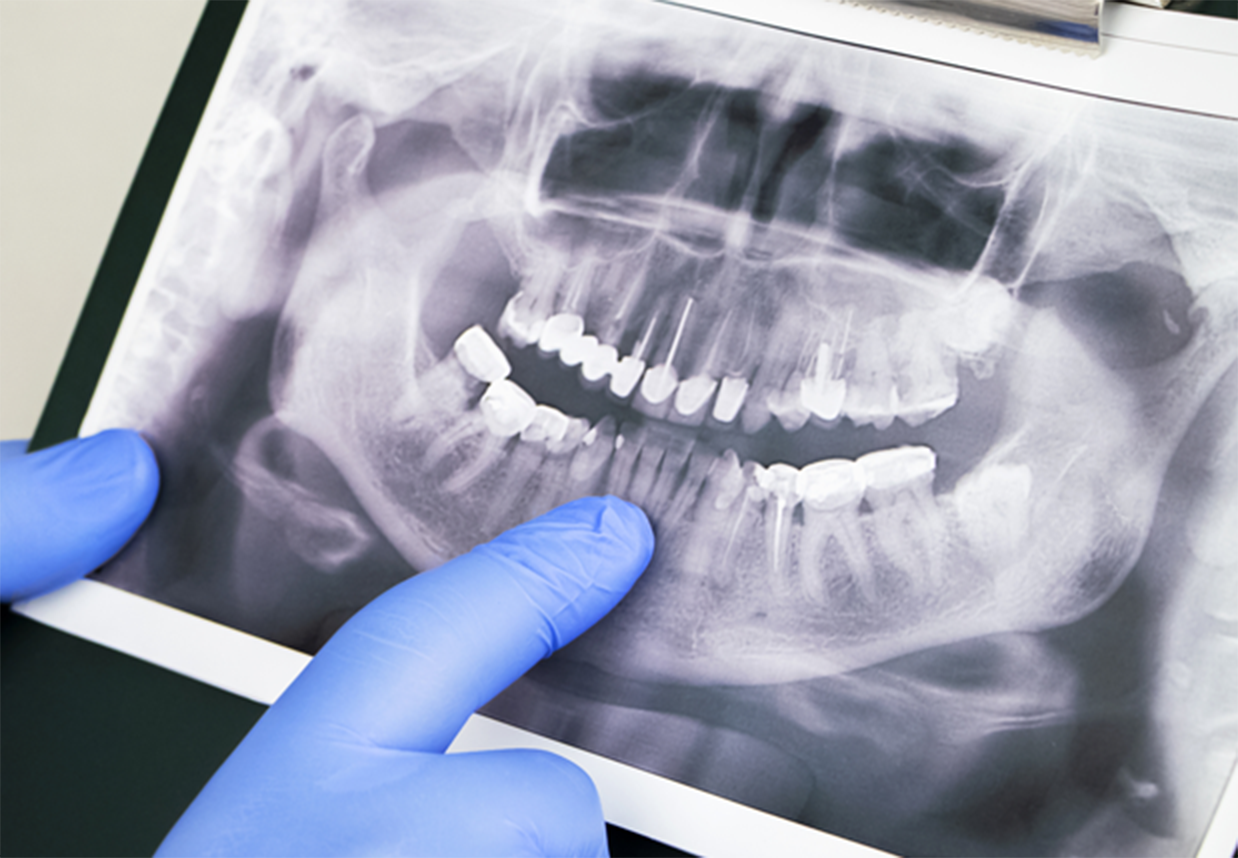

「親知らず」という言葉は皆さん聞いたことがあるかと思います。「一番奥に生えている歯」というイメージがあるかもしれませんが、誰でもそれに当てはまるわけではありません。たしかに、親知らずは永久歯の中で一番最後に生える歯で、通常は上下の顎の左右に計4本あります。しかし、もともと親知らずがない方がいたり、4本すべて生えてこないという方もいたりします。生える年齢としては、永久歯が15歳くらいで揃うのに対し、親知らずは20代ごろに現れます。

親知らずが問題とされるのは、主に正常に真っ直ぐ生えてこないケースです。少し傾いて隣の歯に当たったり、真横に生えて隣の歯を押し出すような状態になったりすることがあります。また、歯肉に埋もれる形で横向きに生えることもあります。親知らずが正常でない向きに生えると、歯磨きがいき渡らず汚れがたまります。すると、歯肉の炎症や虫歯・歯周病を引き起こしやすくなり、親知らずが痛みます。また、隣の歯の虫歯や歯周病の原因となることもあります。

歯の根っこの炎症や膿などの状態によっては、一般的な根管治療では治療できないケースがあります。このような場合は病巣である歯の根っこを切除(歯根端切除)し、根元から薬を詰めて密封する(逆根管充填)処置をすることがあります。その後は経過観察を続け、順調な経過をたどれば歯を支える骨が再生していきます。 基本的には説明、手術当日、抜糸の計3回通院していただき、その後は数ヵ月ごとに検診を受けながら経過観察します。